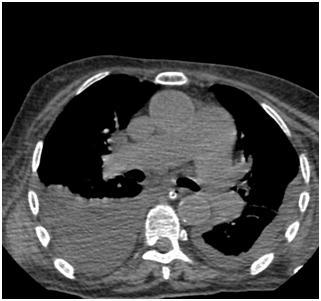

![]() | ![]() |

Двусторонний гидроторакс (компьютерная томография органов грудной клетки).